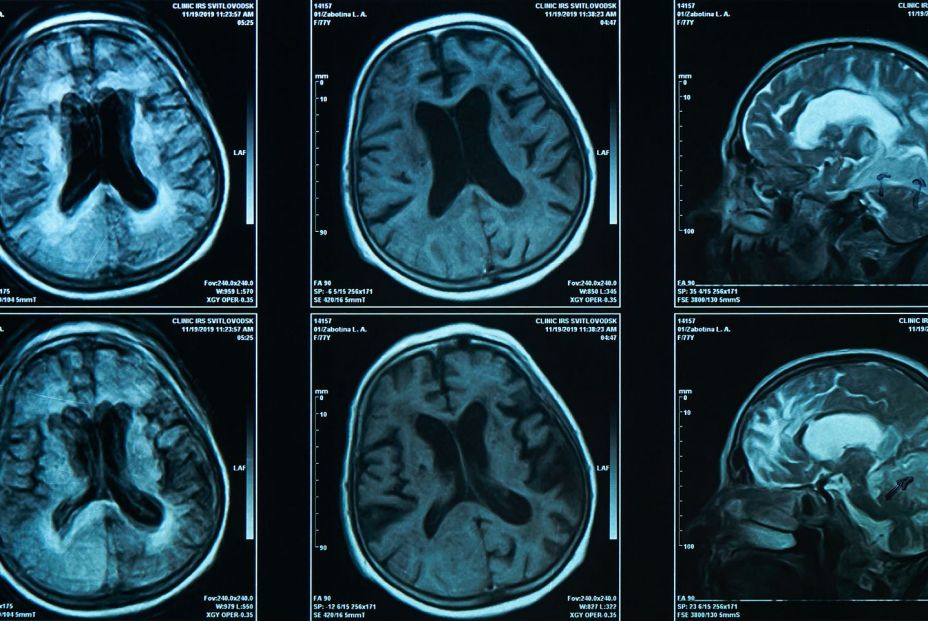

Solo el 16,1% de los pacientes acceden a pruebas de biomarcadores para detectar alzhéimer en España, a pesar de que más del 80% de los especialistas las consideran fundamentales para diagnosticar esta enfermedad neurodegenerativa, según la encuesta multinacional Adelphi Real World Dementia.

El estudio, que ha sido presentado durante la Alzheimer Europe Conference 2025, muestra que esta brecha también existe a nivel internacional, pues atendiendo a la media de los países analizados, únicamente el 15,2% de los pacientes accedió a las pruebas de biomarcadores para confirmar la patología específica.

La enfermedad de Alzheimer afecta a aproximadamente 6,9 millones de personas en Europa, unas 800.000 en España, y se prevé que esta cifra casi llegue a duplicarse para 2050 debido al envejecimiento de la población.